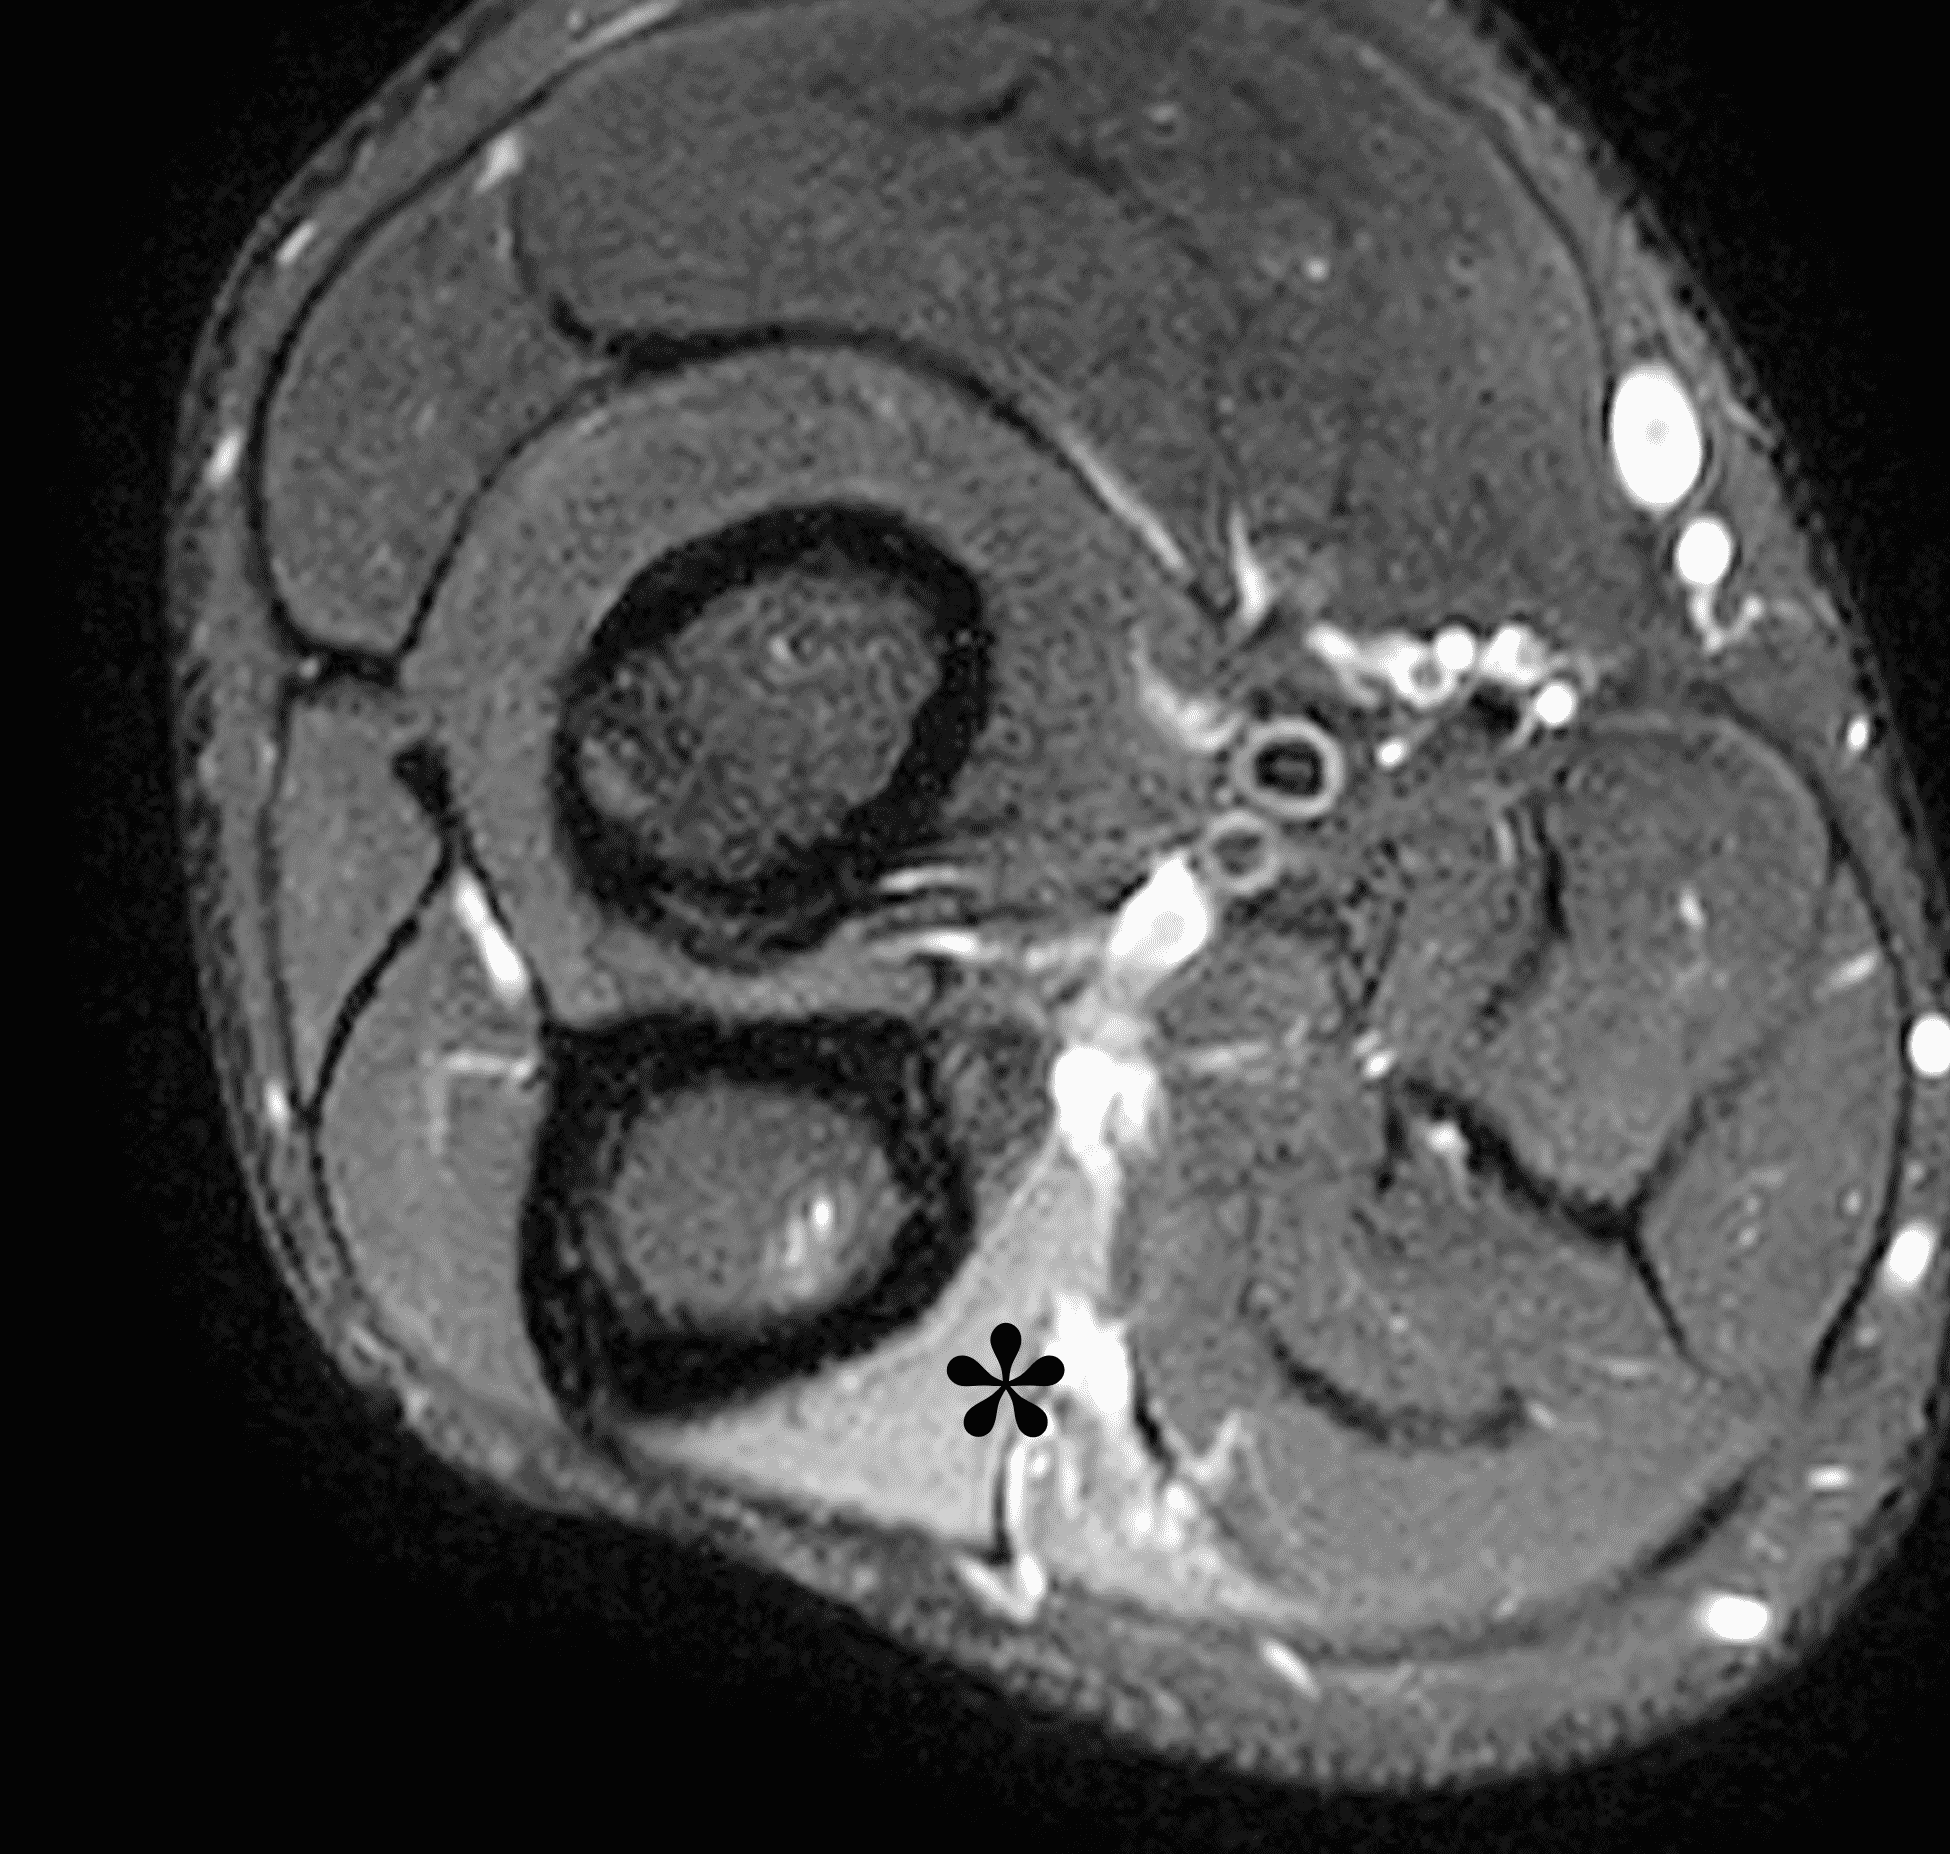

Figure 10: 32-year-old man with a post-traumatic neuroma that developed following an ulnar nerve laceration. Axial (10A) T1-weighted and (10B) fat-suppressed, fluid-sensitive sequences demonstrate enlargement and disorganized architecture of the ulnar nerve (arrows) proximal to the cubital tunnel. (10C) On a sagittal fat-suppressed, fluid-sensitive image, no nerve fibers are visible posterior to the medial epicondyle (ME) in the cubital tunnel (yellow arrow), the site of the nerve transection. The post-traumatic neuroma (red arrow) involves the proximal nerve stump. (10D) An axial fat-suppressed, fluid-sensitive image in the proximal forearm shows subacute denervation with the flexor digitorum profundus muscle (asterisk).